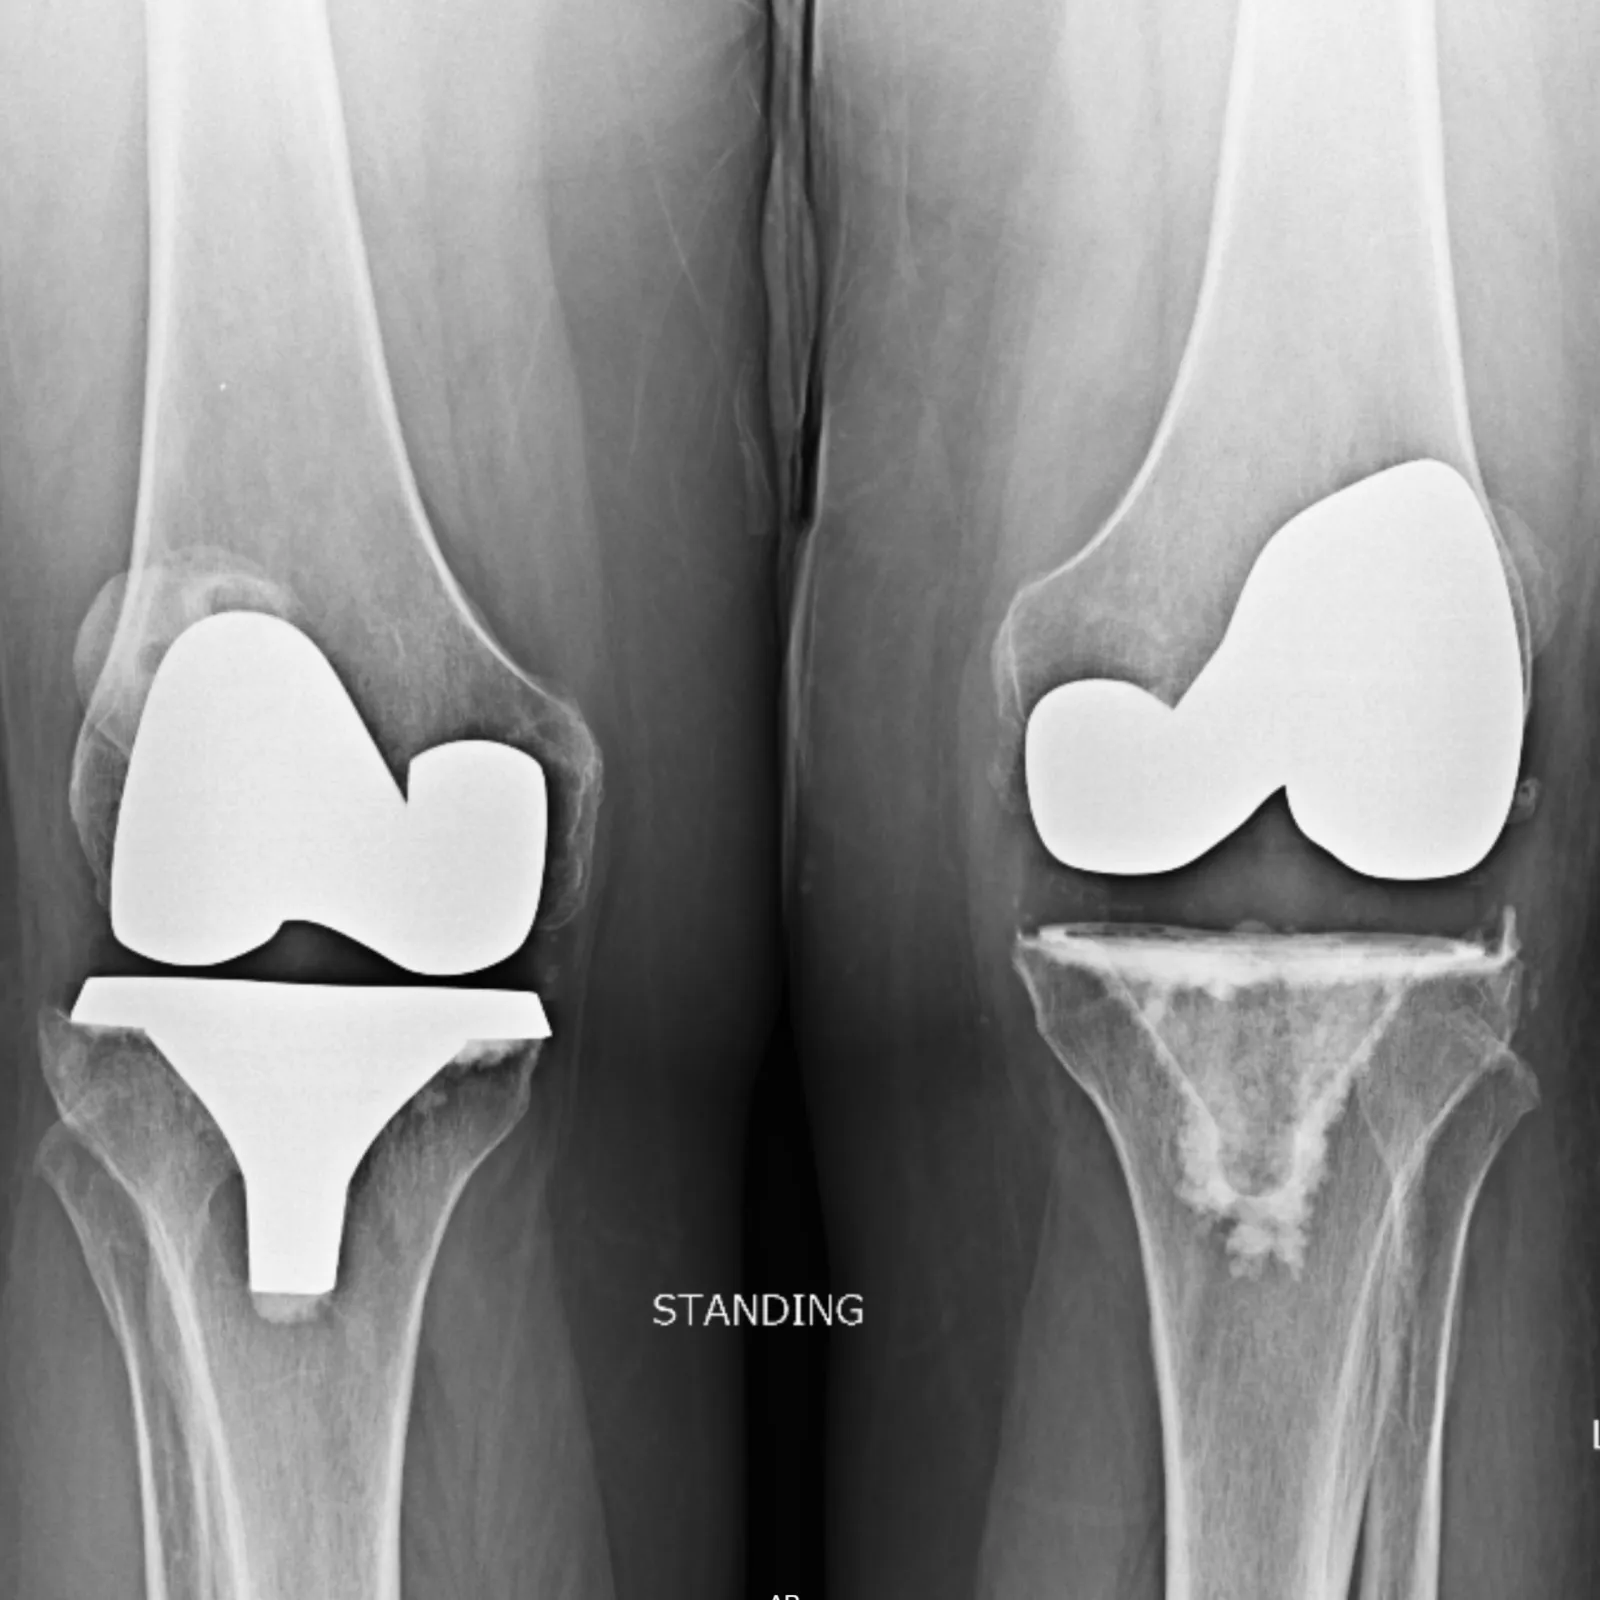

"This was my first time as a patient of Dr. Denehy. I had a prior right knee and hip replacement by Dr. Balthrop [retired]. My left knee was bone on bone and I was in terrible pain. During my visit, Dr. Denehy informed me I needed a knee replacement.

"I admit I was a little nervous but could not have asked for a better crew to get me ready for my surgery . Mark and Becky and Dr. Denehy were awesome. My healing time and therapy was quick with very little pain.

"I am able to now do little things that most people take for granted. Things like shopping, going out to eat, etc. and enjoying life again!

"I have had lots of surgeries in the past but this one was the smoothest. I have been a part of BGO for a long time and will continue to be their patient when needed. If anyone is on the fence about having knee or hip replacement, I highly recommend to go ahead and get it done - the sooner the better. It is not worth all that pain and I highly recommend BGO and Dr. Denehy. Thank you Dr. Denehy, and all you have done for me. It is not forgotten.

"I love to fish and it has been a long time since I have been able to enjoy it because of my knee problems. I am getting ready to go fishing now and get to enjoy life again, Thanks to Dr. Denehy."